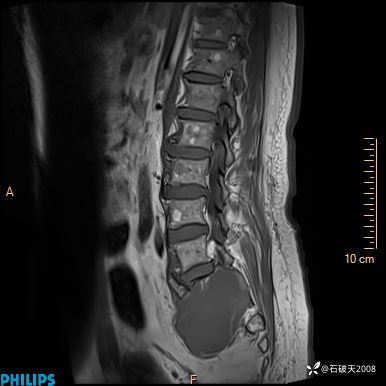

2023年3月份MRI影像

T2矢状位压脂